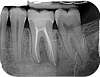

radiographie dentaire

N°2

Radio dentaire